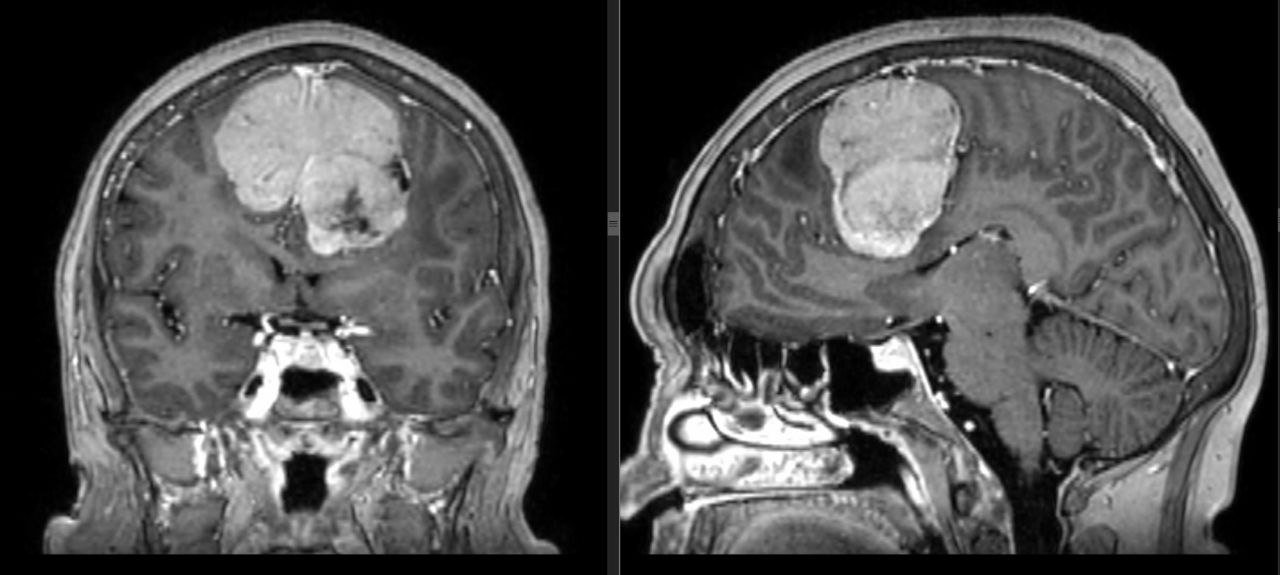

Врачи Ижевска удалили гигантскую опухоль головного мозга у 60-летней женщины

Врачи Ижевска удалили гигантскую опухоль головного мозга у 60-летней женщины Ижевск. Удмуртия. В Ижевске врачи ГКБ №7 прооперировали 60-летнюю женщину с гигантской опухолью мозга. Об этом сообщает пресс-служба Минздрава Удмурт …